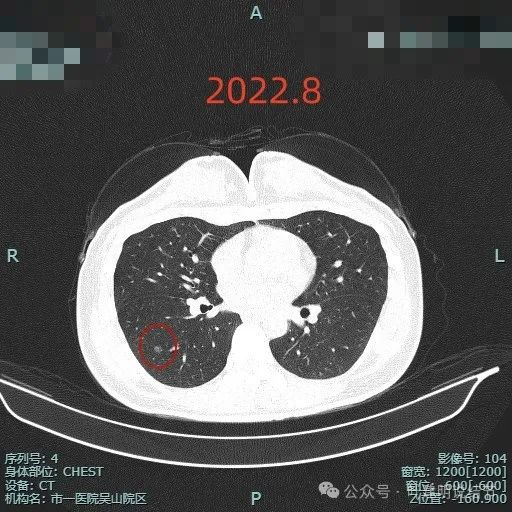

肺磨玻璃结节术后病理是不典型增生,这刀白开了吗?

病史摘要:患者主因“检查发现肺部阴影5年”就诊。5年前当地医院体检胸部CT提示肺部结节,无明显症状未治疗。2024年11月杭州市肿瘤医院复查胸部CT,右肺多枚小结节,LUNG-RADS 2,建议年度随诊。现患者无不适,为求进一步诊治入院。起病以来,患者神志清,精神、胃纳、睡眠、二便正常,体重无明显变化。诊疗过程:体格检查未提及。多次胸部CT显示右下叶磨玻璃结节,轮廓与瘤肺边界清楚,